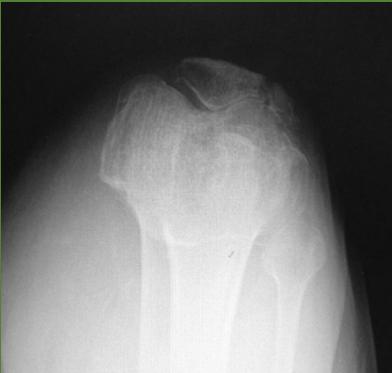

Imaging Studies

- Standard Radiographs:

- Both knees AP standing views (weight-bearing)

- Lateral views of both knees

- Skyline view (patellofemoral assessment)